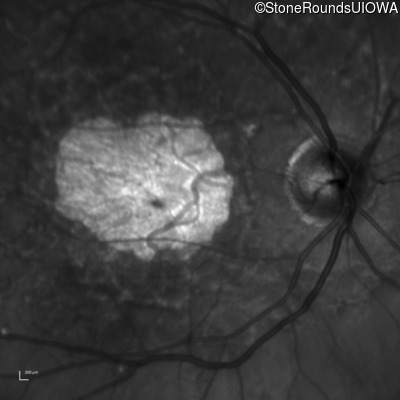

Infrared Fundus Photograph - Right - 20/125

Exemplar